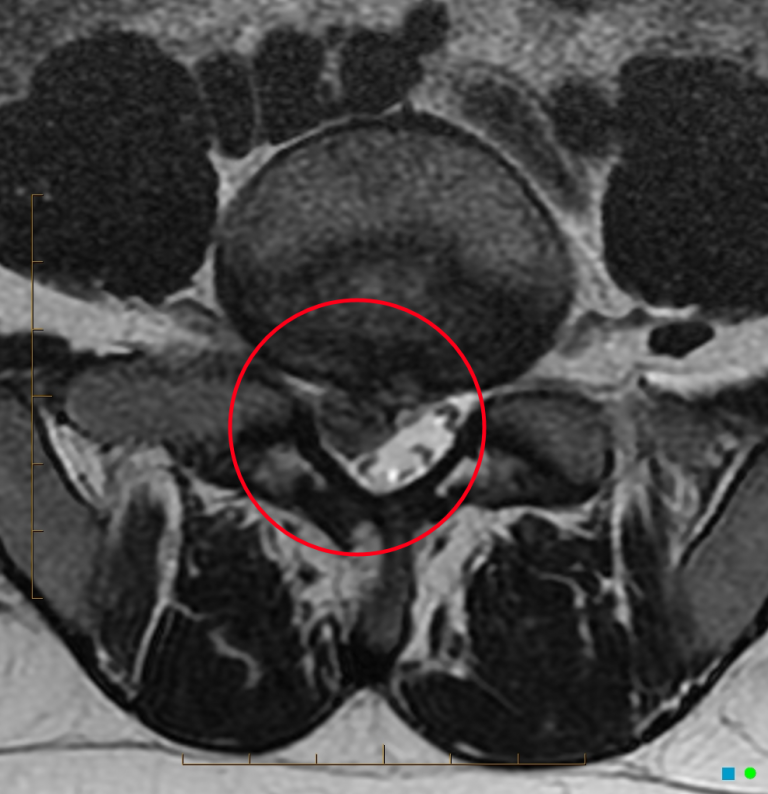

Kann man eine Entzündung im MRT sehen? Ob Knochen, Muskeln, Sehnen, Bänder oder Knorpel - mit einer MRT-Untersuchung können Schädigungen, Veränderungen, Entzündungen und grobe Verkalkungen am gesamten Bewegungsapparat exakt beurteilt werden. Besonders hervorzuheben ist jedoch die Rolle des MRT im Kontext entzündlich-rheumatischer Erkrankungen wie der Rheumatoiden Arthritis, dem Morbus Bechterew, der Psoriasis Arthritis oder der reaktiven Arthritis

Besonders hervorzuheben ist jedoch die Rolle des MRT im Kontext entzündlich-rheumatischer Erkrankungen wie der Rheumatoiden Arthritis, dem Morbus Bechterew, der Psoriasis Arthritis oder der reaktiven Arthritis Bei diesen Autoimmunerkrankungen sind häufig Gelenke und Weichteile wie etwa Sehnenansätze entzündet. Die weißen Flecken, die man auf MRT-Bildern sieht, stellen Flüssigkeit dar

Mrt Berlin Mitte Wissenswertes Zu Der Mrt. Während das MRT je nach Körperregion 20-60 Minuten benötigt (detaillierte Informationen in der Übersicht zur Kernspintomographie), ist das CT schon nach 1-5 Minuten. Im Falle einer MRT vom Kopf können die weißen Punkte unter anderem als Liquor (Hirnwasser), Narbe oder Entzündung gedeutet werden.